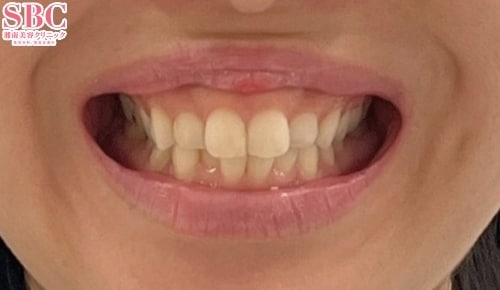

施術後12ヶ月後

段差も重なりも改善されました★